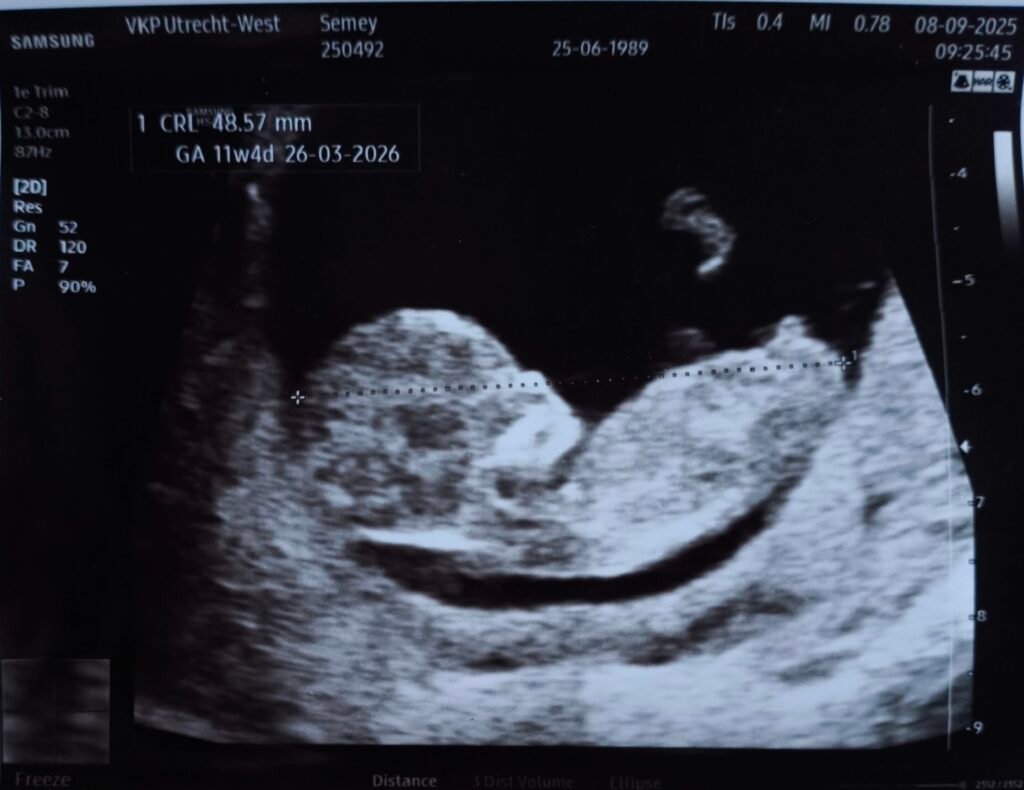

Second Echo

09/09/2025

Now you can really tell that the clump of cells resembles a little human. With a large head, nose, ears and a little foot.

Currently the baby is 48.57mm and has been baking for 11 weeks and 4 days.

The due date is officially set to March 26, 2026.